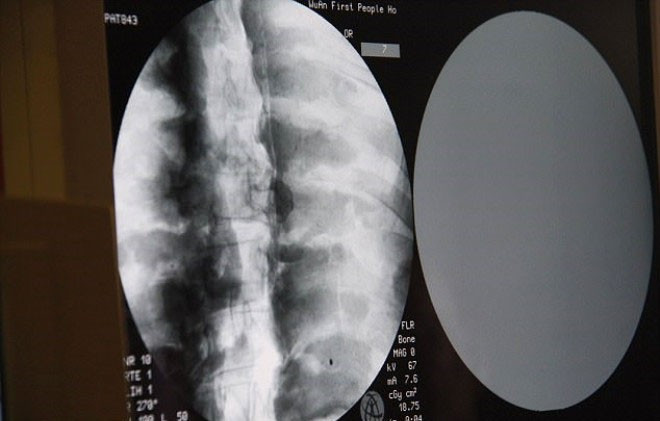

Tapınağın yönetimi, Ci Xian'ın cesedi için CT taramasını 8 Temmuz'da düzenledi. Doktorlar, Usta Ci Xian'ın, hala sağlıklı kemikleri ve bir beyni bulunduğunu söylediğinde, keşişler şok geçirdi.

Yapılan incelemede rahibin kemiklerinin hiç bozulmadığı ve beyninin zarar görmediği ortaya çıktı.

Üst çene, üst dişler, kaburga, omurga hepsi yerinde duruyor.